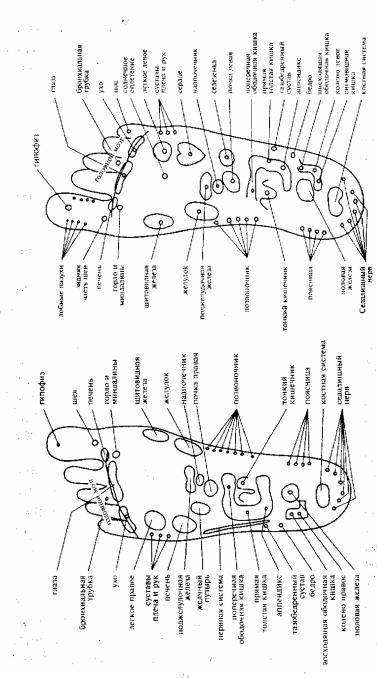

Как может кишечная трематода вызвать рак? Типичное место пребывания этого паразита — кишечник, где он может вызвать небольшие нарушения типа хронического колита, болезни Крона, острые колики в кишечнике... Но если этот паразит внедряется в различные органы, такие, как почки, печень, в матку, предстательную железу, он может нанести значительные повреждения. Исследования д-ра Кларк показывают, что если паразиты обосновываются в печени, это вызывает рак. Они начинают жить в печени только у некоторых людей. Это те люди, которые имеют пропиловый спирт в своих телах. Данные Кларк говорят о том, что больные раком имеют оба фактора — пропиловый спирт и листовидную трематоду в их печени. Растворитель пропиловый и изопропиловый спирт стимулирует печеночные клетки задерживать листовидную человеческую трематоду. В этом случае паразиты начинают развиваться в клетках печени. Чтобы развился рак, в вашем теле должны присутствовать два фактора — пропиловый спирт и паразиты. Далее автор открытия подробно описывает развитие рака в организме человека (см. рис. 1,2).

Рис 1. Человеческая кишечная трематода.

О трематодах

Доктор подчеркивает, что для понимания развития рака мы должны понять основные факты о человеческой кишечной трематоде Fasciolopsis buski. Она из семейства листовидных трематод.Этот паразит проходит через определенные факторы развитая от возникновения до воспроизводства потомства. Первая стадия это яйца. Взрослые особи продуцируют миллионы яиц. Яйца выделяются из тела через кишечник. Взрослые особи, однако, крепко держатся за стенки кишечника (или в печени, вызывая рак; или в матке, вызывая эндометрит; или в тимусе, вызывая СПИД; или в почках, вызывая болезнь Ходкина).

Циркарии Метациркарии

Взрослая Яйца

особь

Мирацидии Радии

Рис.2 Жизненный цикл трематоды.